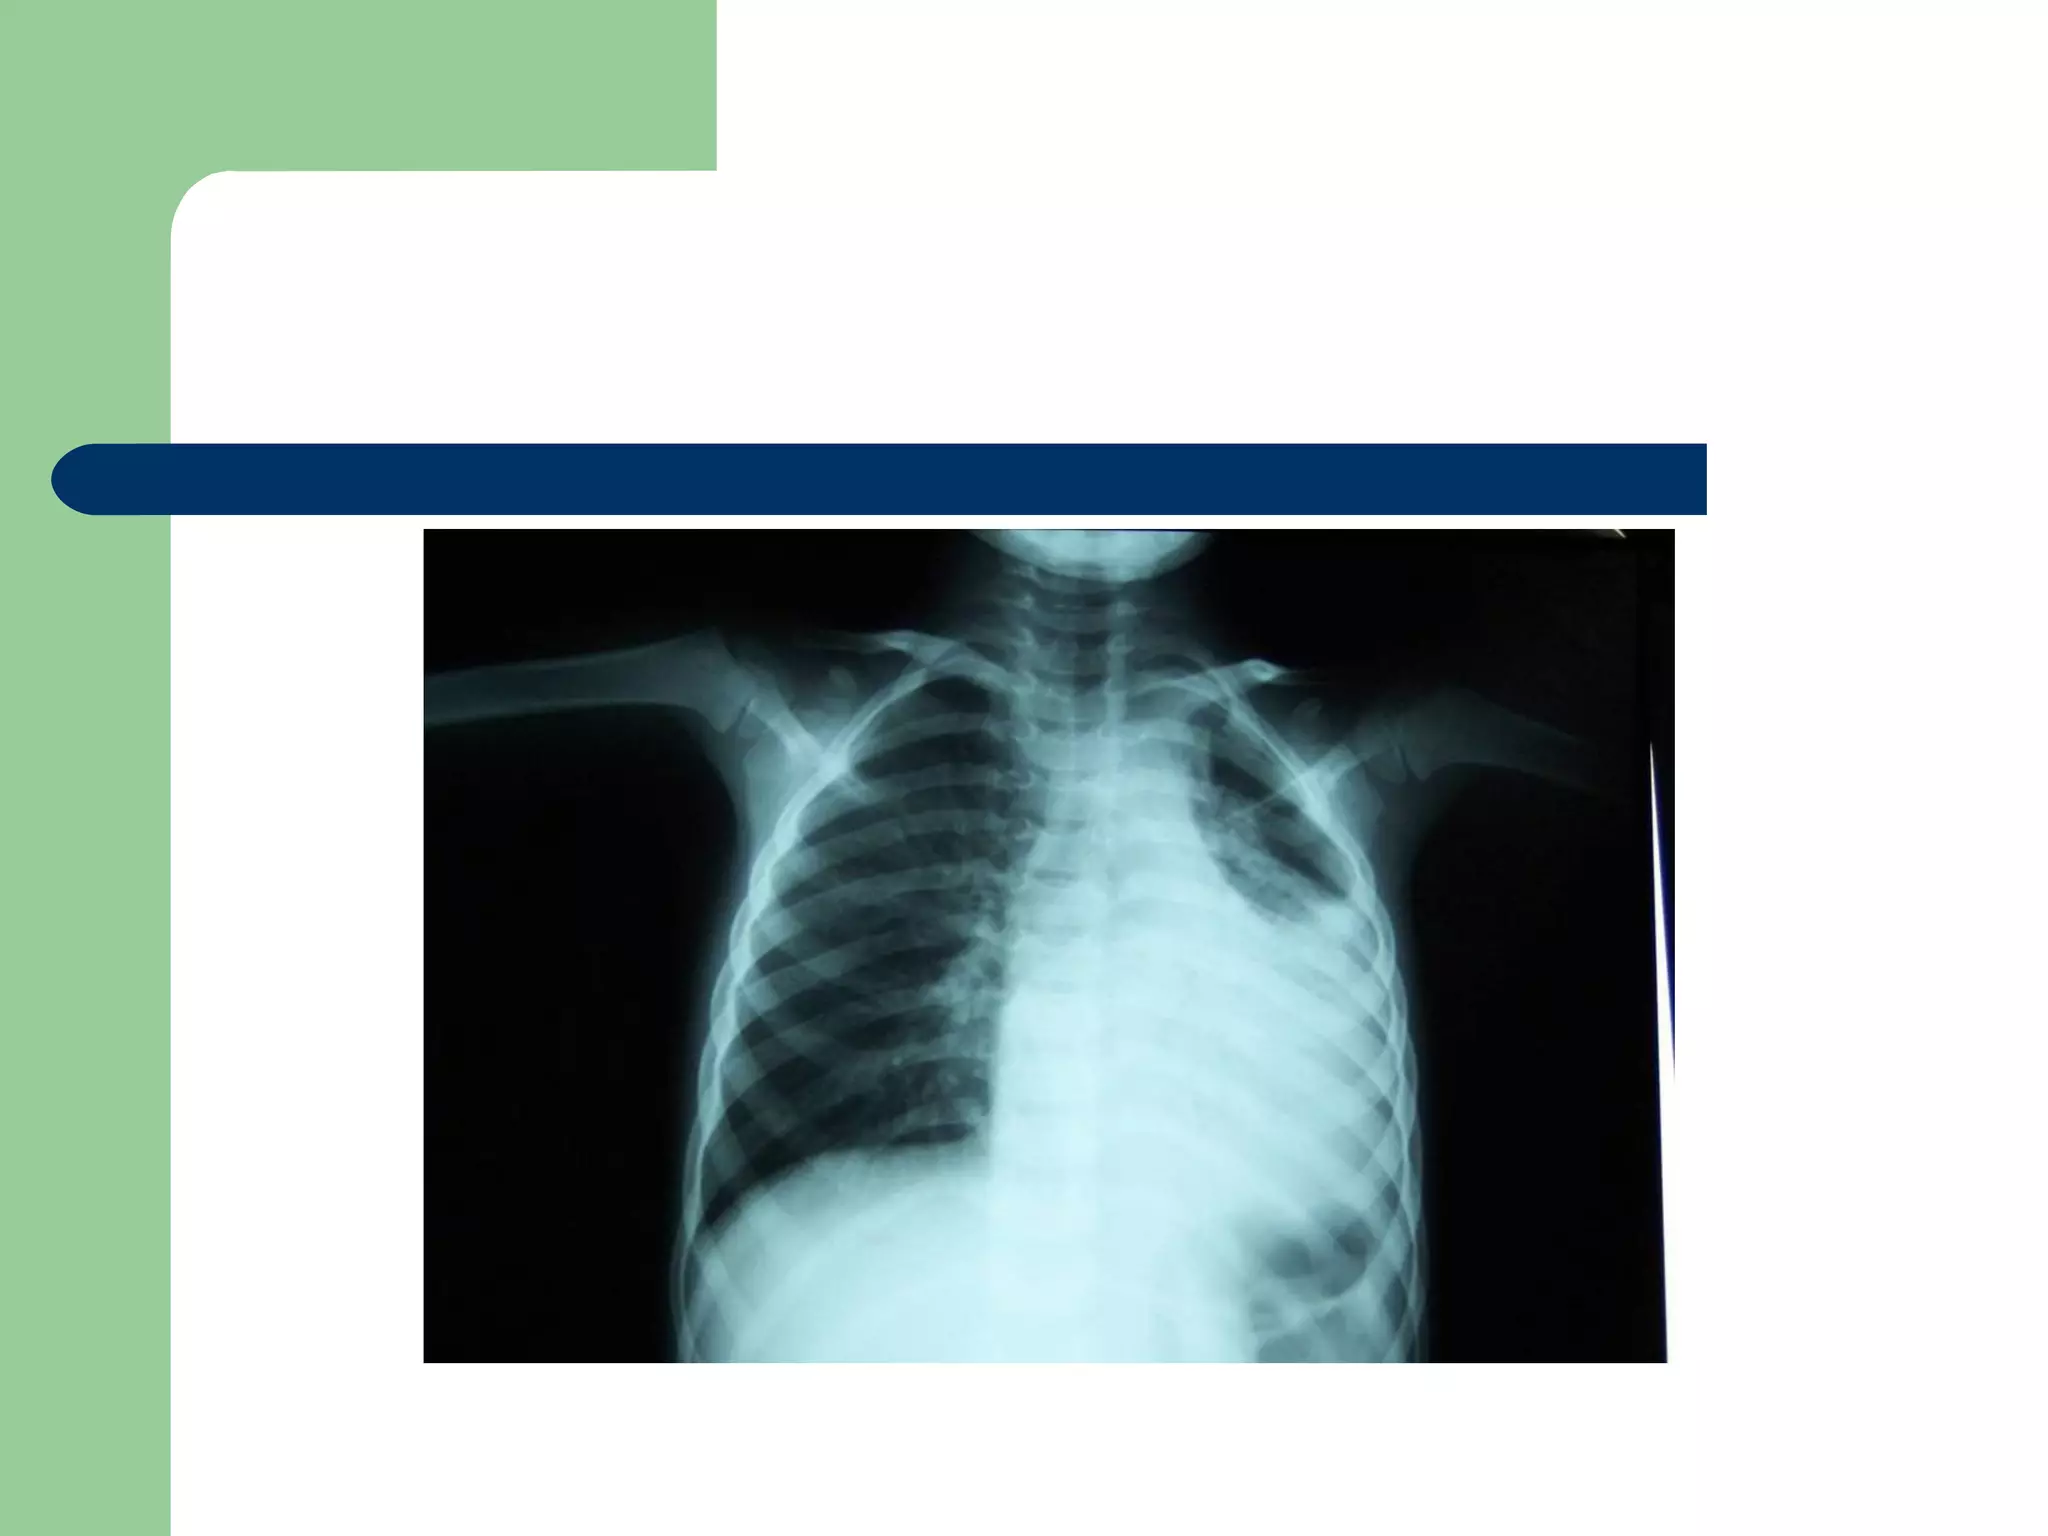

 CXR may be normal if the FB is not radio- opaque.

or it can show a radio- opaque FB such as bone.

Obstructive emphysema: is produced by intra-bronchial

FB that allows air to enter in inspiration and prevents its

exit in expiration.

Lung collapse (complete or partial) is produced by a FB

that blocks the bronchus completely.

Unresolved pneumonic consolidation.

A five and a half yr old boy: non-resolved cough

Of 40 days duration

DIAGNOSIS…  Examination:signs of respiratory distress may be present.  CXR may be normal if the FB is not radio- opaque. or it can show a radio- opaque FB such as bone. Obstructive emphysema: is produced by intra-bronchial FB that allows air to enter in inspiration and prevents its exit in expiration. Lung collapse (complete or partial) is produced by a FB that blocks the bronchus completely. Unresolved pneumonic consolidation. Lung abscess or broncheictasis are caused by a long-standing FB.

A five anda half yr old boy: non-resolved cough Of 40 days duration